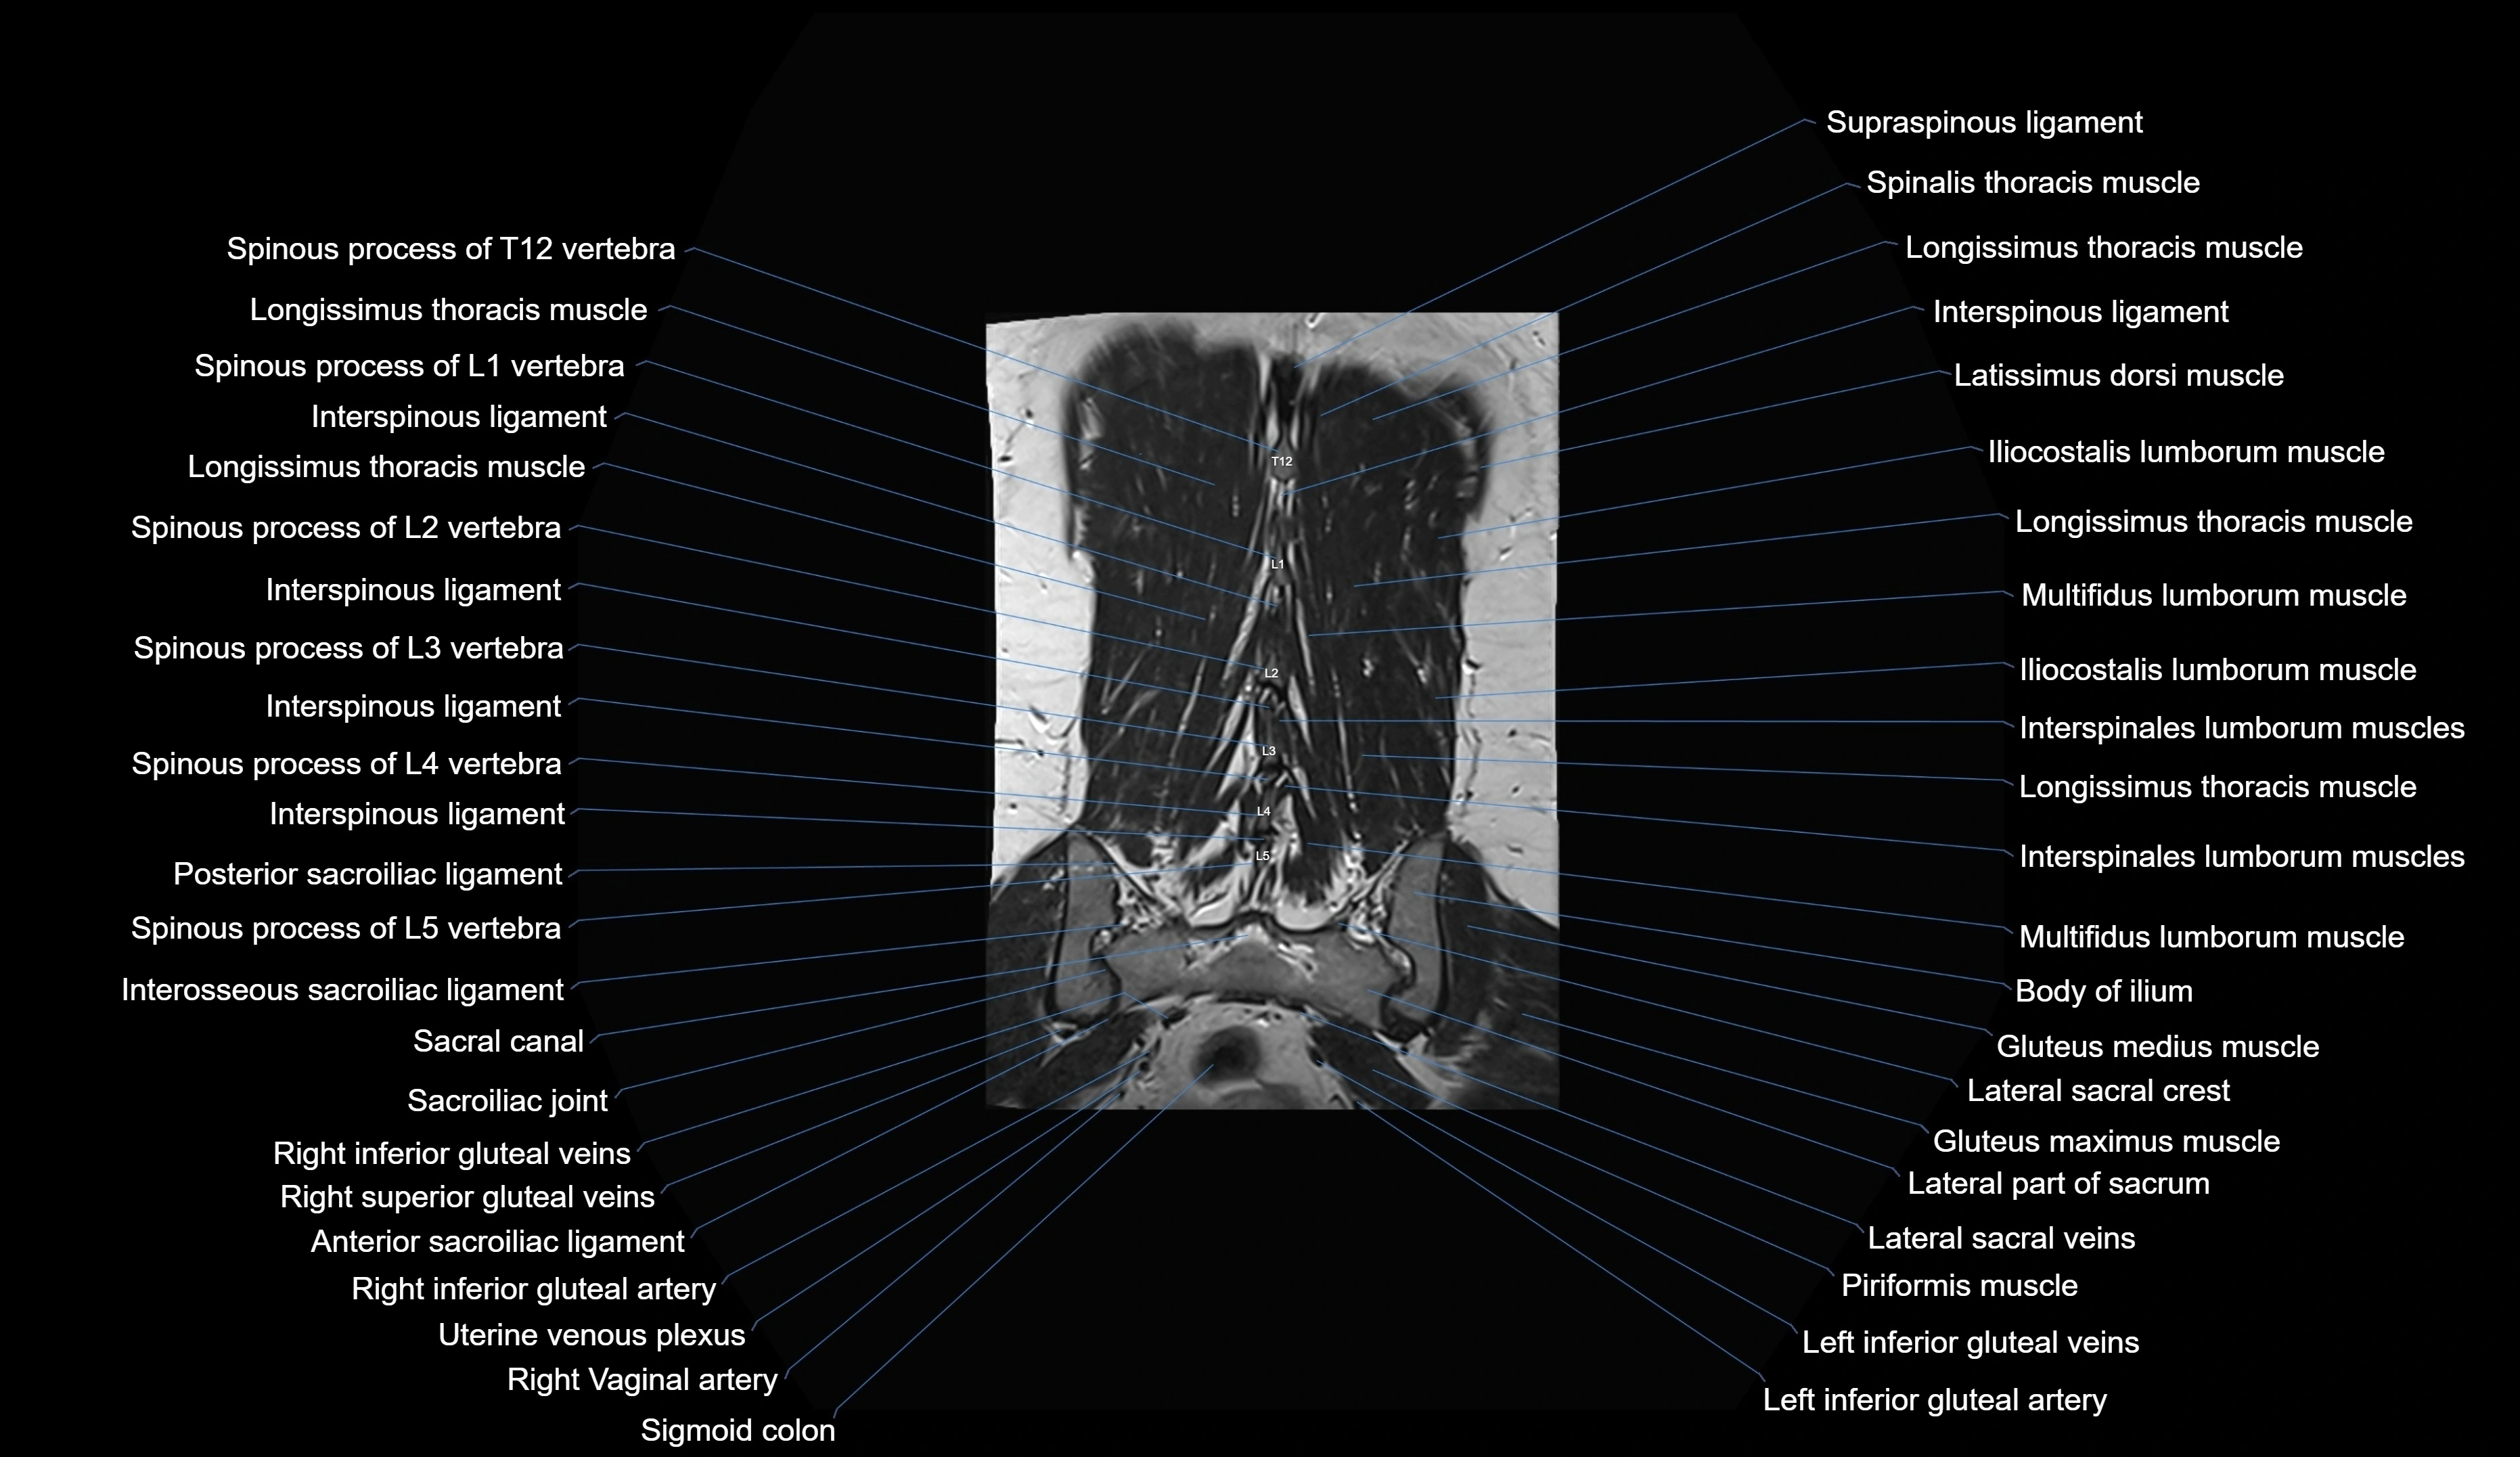

MRI images